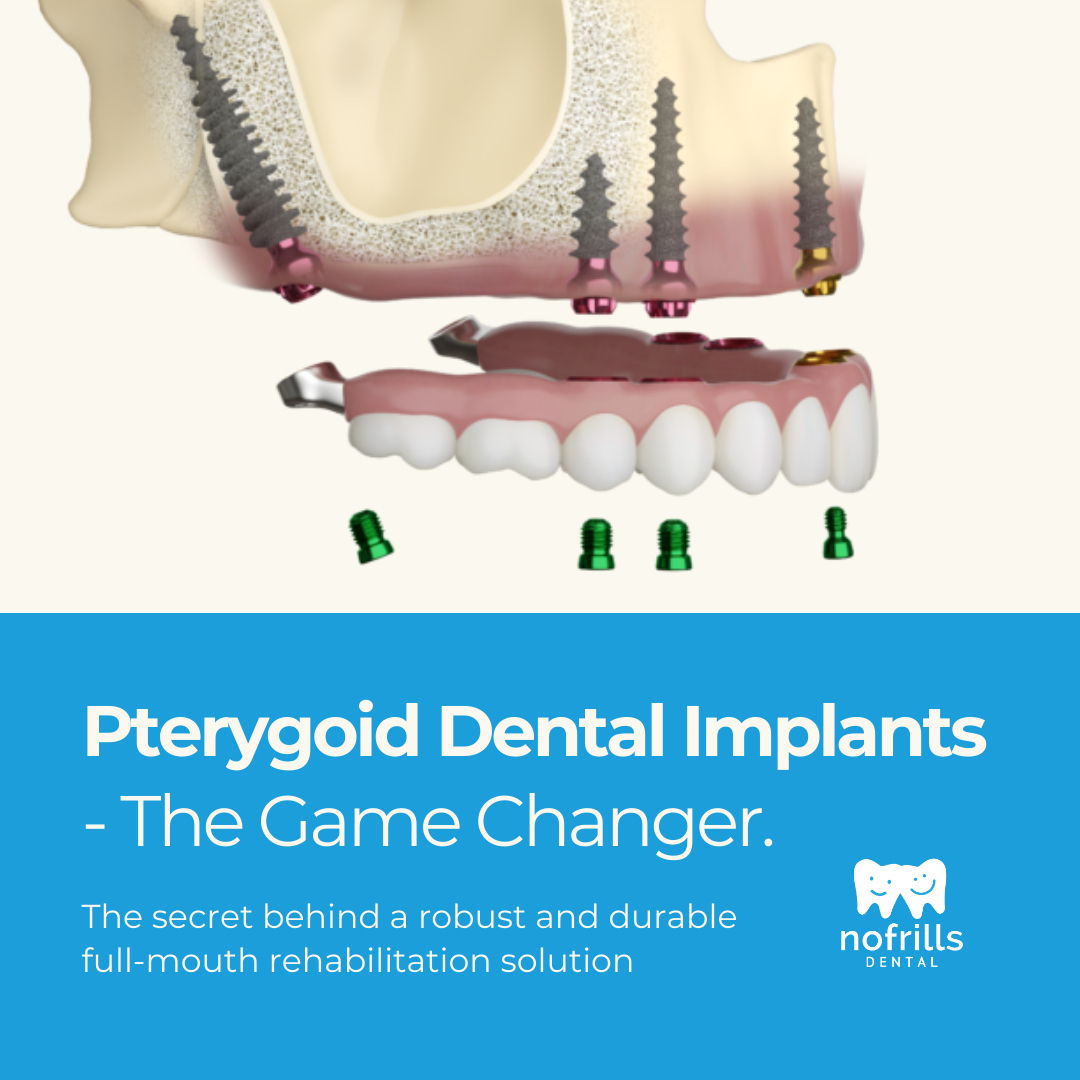

Pterygoid Dental Implants: An In-depth Guide

Dental implants have revolutionized the world of dentistry, offering solutions for patients with missing teeth. Tubero Pterygoid Dental Implants stand…